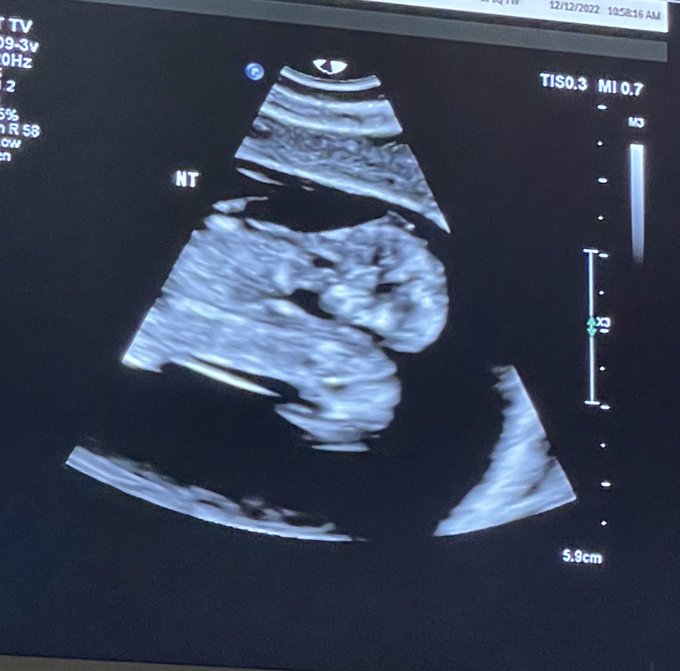

Then, at 10 weeks, Nicole experienced such intense pain in her abdomen that she went to the emergency room at 2:00 in the morning. It was there that she and Austin learned they were having twins — but that the twins were conjoined.

The following day, a more extensive ultrasound was carried out, revealing that the girls shared a heart, a liver, a diaphragm, bowels, and one umbilical cord in one gestational sac. They also showed signs of having chromosomal abnormalities. The doctors told Nicole and Austin that the pregnancy was not viable, and the chances of miscarriage were even greater than the chances of survival. They asked the couple if they wanted an abortion.

At 20 weeks, the twins underwent a fetal echocardiogram, and it was determined that the heart they share has four chambers, but two left aortas. Nicole returns to the hospital every two to three weeks to check the twins for signs of heart failure, and to make sure the fluid and placenta are good, and so far, they have been doing well and continue to grow.

Update 5/16/23: Conjoined twins Maria and Rachel’s scheduled C-section has been moved up from June 2 to May 16. According to their mother Nicole’s Instagram account, “[T]heir growth is starting to slow down now and so is their heart. We are now preparing to meet our babies on Tuesday, May 16th. They will be 32 weeks along then. Definitely nervous, but we are putting all of our trust in God! We are praying for them to be born alive so they can be baptized right at birth. I have already received my first steroid shot to help with their lung function.”